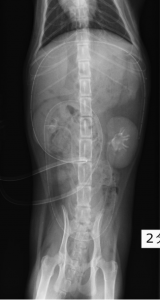

術後数日後に排泄性尿路造影した写真です。左右に2.1Frの尿管ステントと腹腔内に透析用のチューブが留置されています。